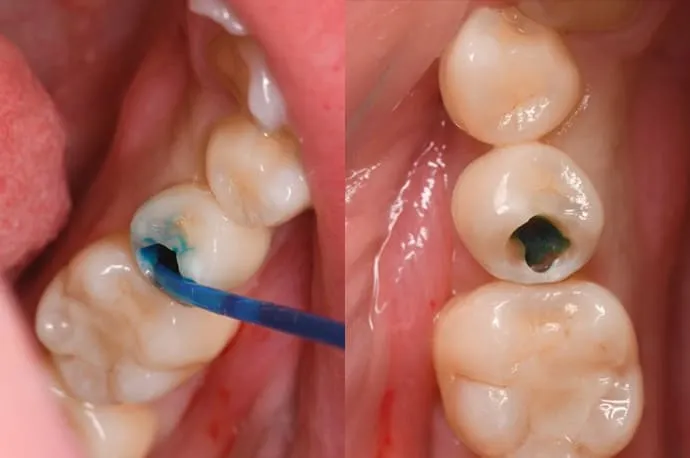

虫歯除去の流れ

一見すると穴が空いていないように見えますが、内部で虫歯が広がっている状態です。

歯の表層を削ると、中は大きな空洞になっています。

虫歯を染める専用の薬剤を使い、どこまで虫歯が広がっているかを確認します。

染色液で染まった部分を丁寧に除去し、再度染めて確認します。この作業を繰り返し、染まらなくなるまで行います。虫歯は健康な歯に比べて柔らかいため、回転切削器具だけでなく、手作業で少しずつ取り除くこともあります。染色液だけでなく、触ったときの硬さも目安にします。

虫歯の除去が完了すると、かなり大きな空洞になっています。中央の少し青く染まっている部分は、歯の神経が露出している状態です。このように大きな虫歯の場合は、修復の前に根管治療が必要になります。